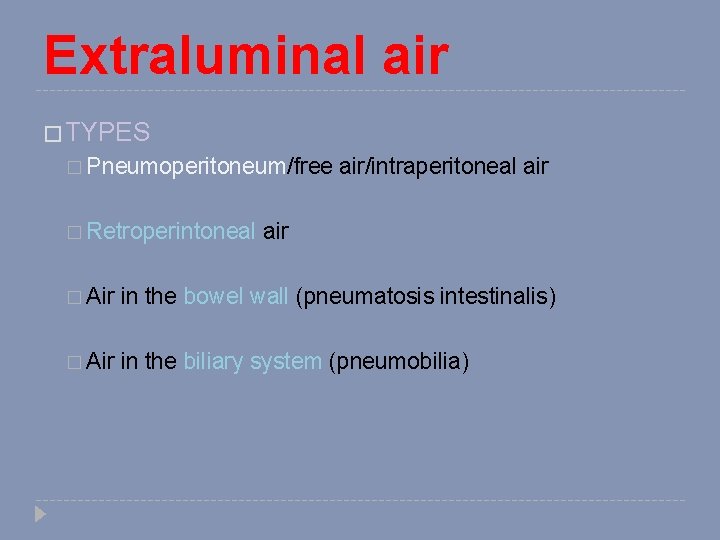

Extraluminal air � TYPES � Pneumoperitoneum/free � Retroperintoneal air/intraperitoneal air � Air in the bowel wall (pneumatosis intestinalis) � Air in the biliary system (pneumobilia)